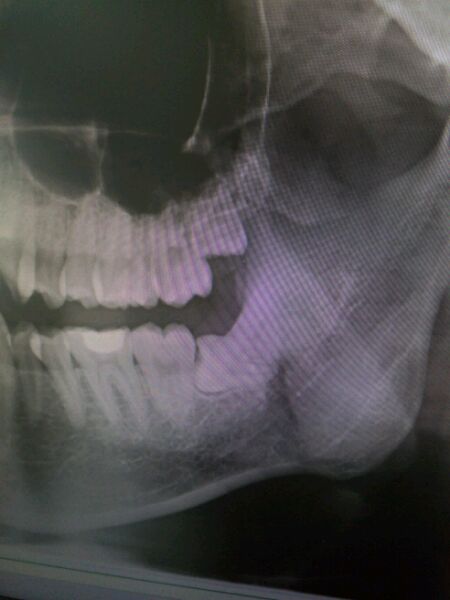

【智齿】医生来看看我这个,吓死了。

你的牙好像有些拥挤啊

本来是上面的牙发炎,消肿后今天拔了拍个片发现了更大的问题,唉

左下那颗算不算横生,价格怎么样